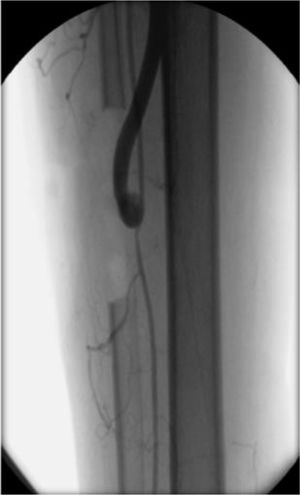

Se realizó por primera vez un bypass en T invertido en nuestro servicio en un caso complejo de enfermedad oclusiva femoropoplítea y distal, sin vena adecuada y con 2 vasos de run-off inadecuados9. Para optimizar el flujo de salida, los autores crearon un bypass venoso corto entre las dos arterias de run-off, que luego se conectó a la arteria de influjo con un injerto protésico (fig. 7). En teoría, 2 vasos de run-off disminuyen la resistencia arterial periférica, aumentan la velocidad del flujo en el injerto y optimizan la permeabilidad de la revascularización.

Técnicamente, el bypass en T invertido consiste en conectar las 2 arterias diana, a través de injerto venoso corto. Es posible obtener 5-10cm de vena de diámetro aceptable en la mayoría de los pacientes, sea la safena externa o un segmento de safena interna junto al cayado. Se realizan ambas anastomosis distales mediante el uso de un vendaje Esmarch. Luego, se conecta una prótesis (injerto de PTFE heparinizado de 6mm de diámetro) al injerto venoso, cerca de la anastomosis más proximal, para evitar la acción de las válvulas. En seguida se retira el vendaje Esmarch y se realiza la anastomosis final entre la prótesis y la arteria de influjo (generalmente la arteria femoral). En nuestra experiencia, esta técnica es útil para la revascularización directa del pie, en situaciones que cumplan los siguientes criterios: